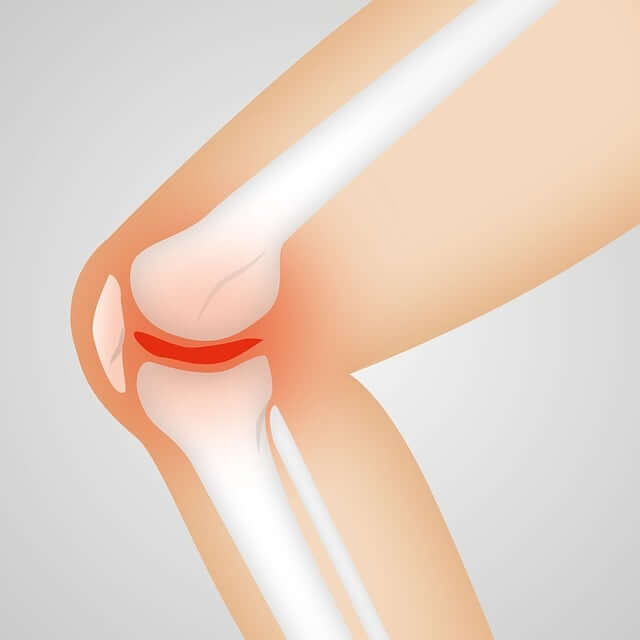

무릎연골파손

무릎 관절연골은 무릎 관절을 보호하는 역할을 합니다. 무릎 관절연골에 손상이 생기면 통증, 부종, 운동 장애 등의 증상이 나타날 수 있습니다.

무릎 퇴행성 변화

나이가 들면서 무릎 관절에 염증과 마찰이 생기는 것이 자연스러운 일입니다. 이러한 마찰은 무릎 통증, 강직성 등의 증상을 유발할 수 있습니다.